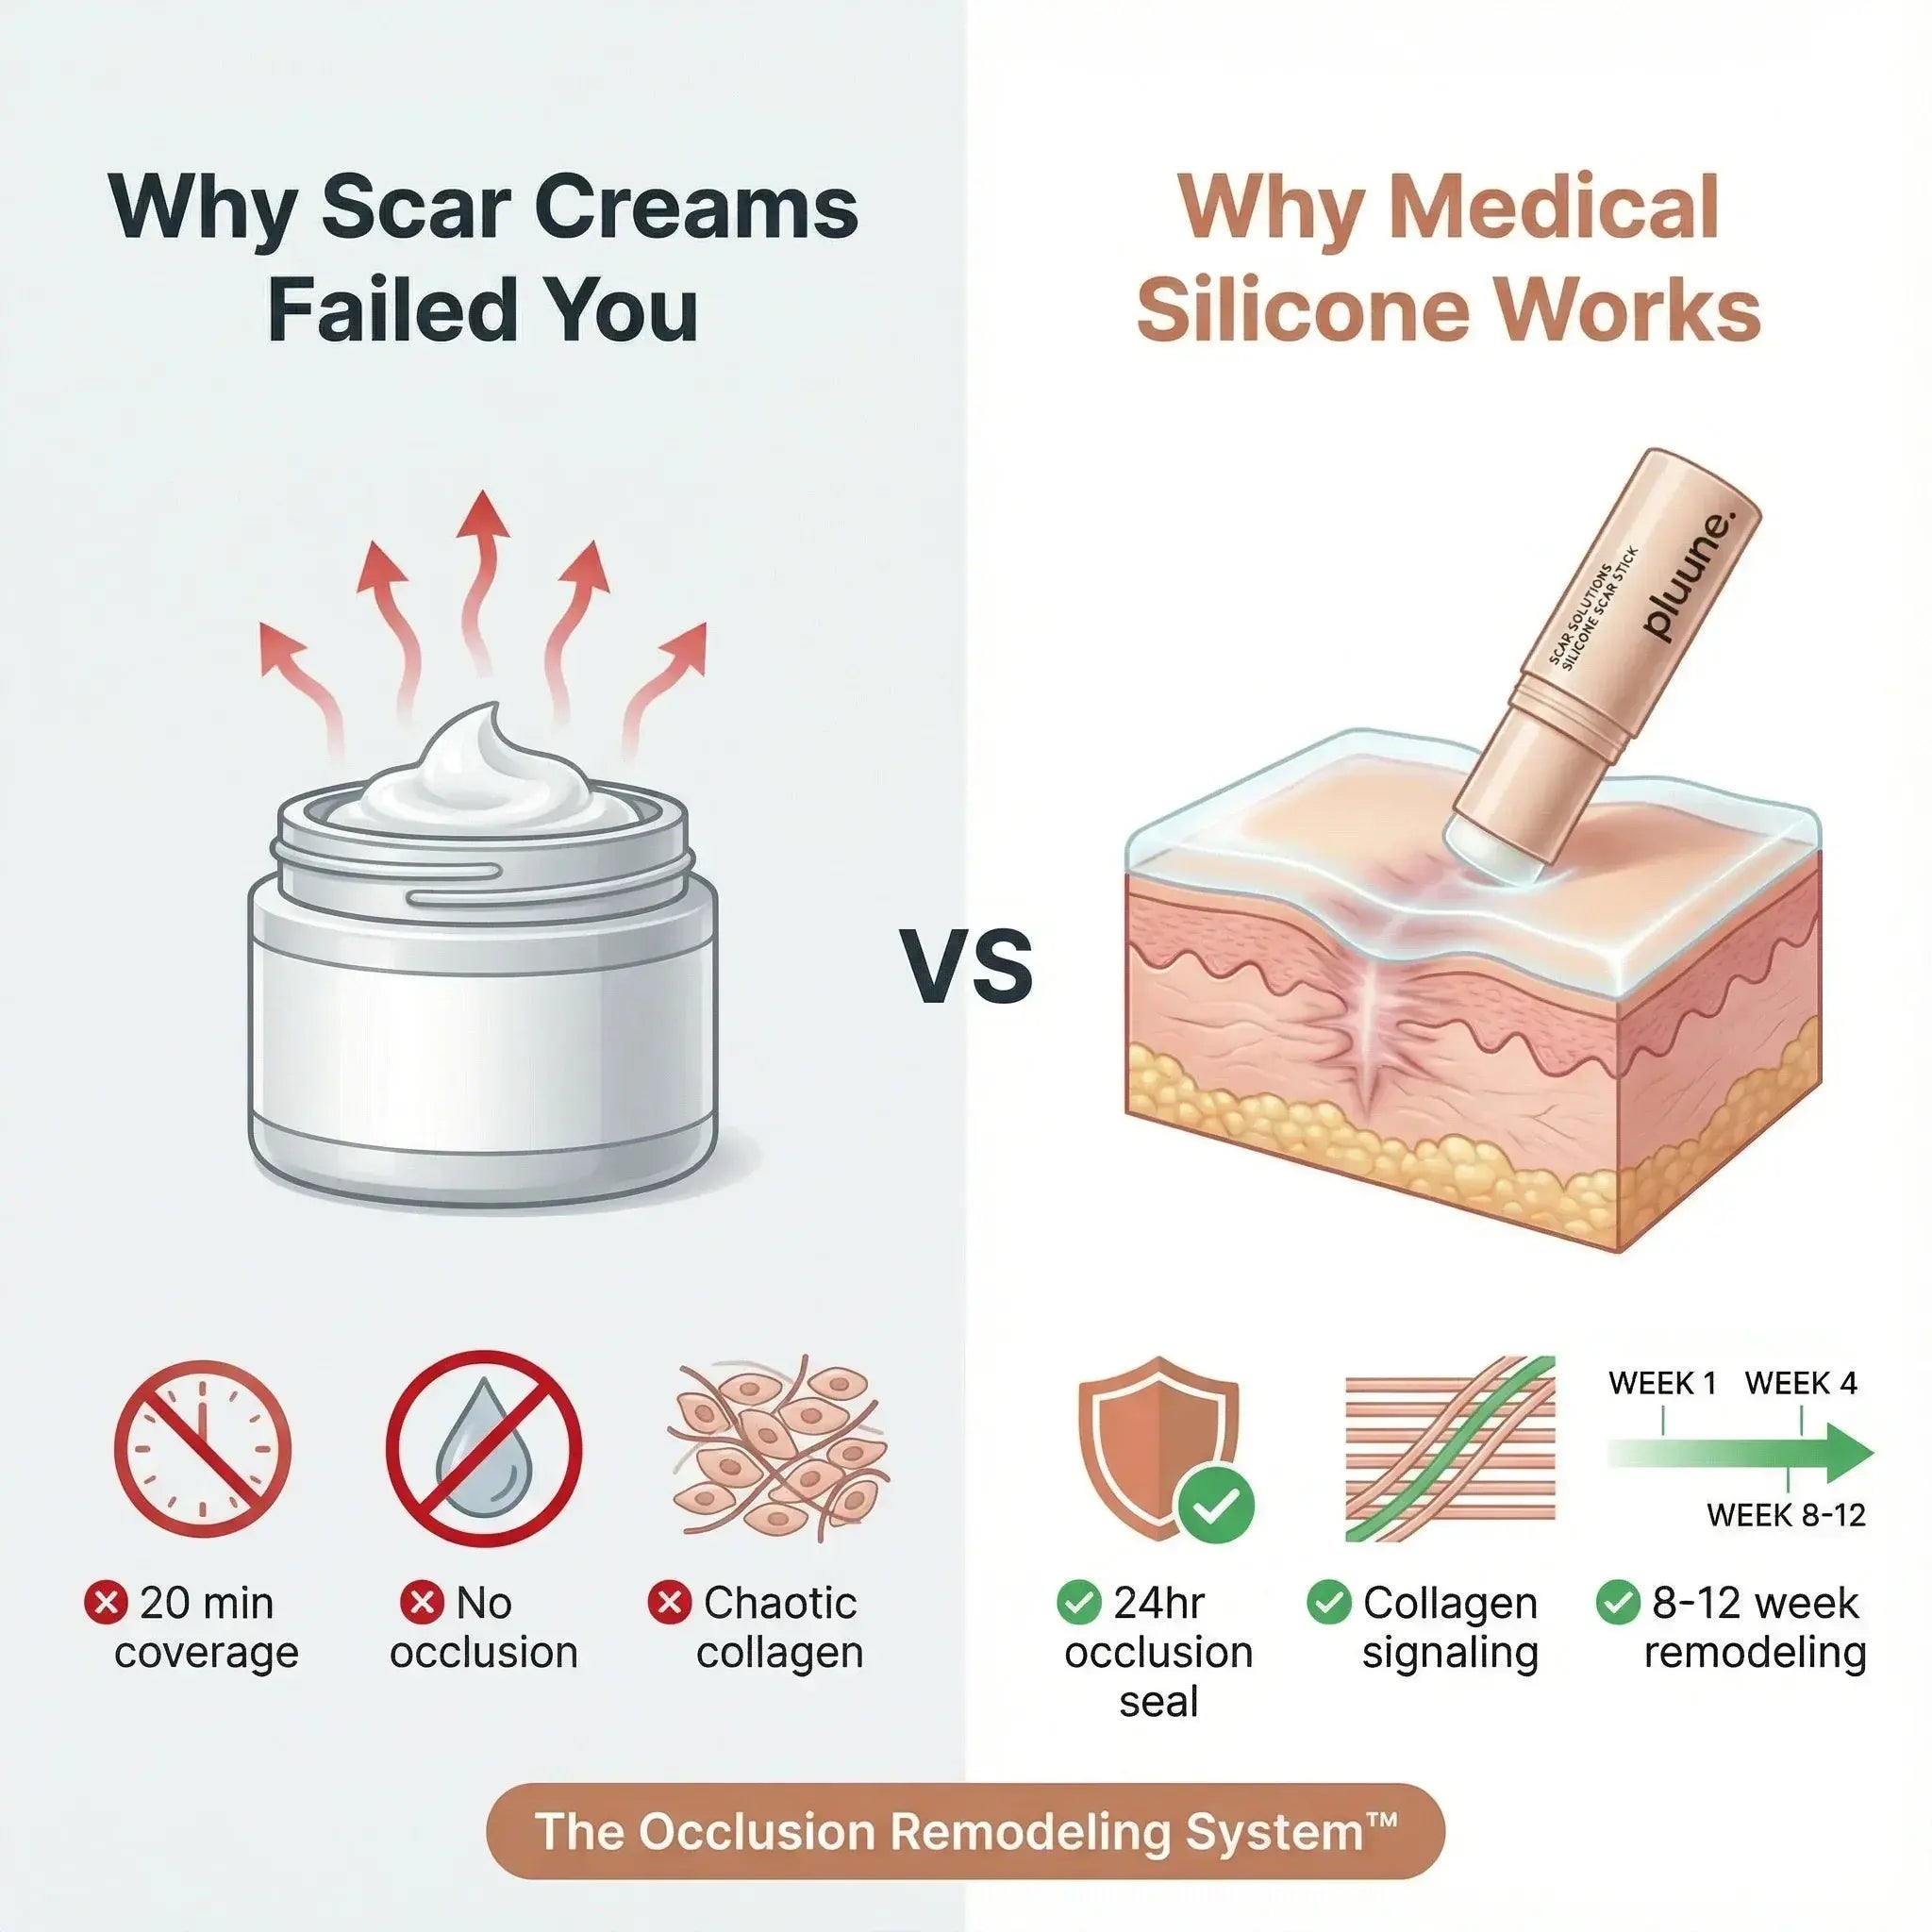

The "Hidden" Hospital Secret Doctors Have Used For 40+ Years

Medical-grade silicone has been the gold standard in hospitals since the 1980s. Plastic surgeons give it to post-op patients. Burn units use it.

So why didn't you know? Beauty companies can't patent it. They sold you vitamin E creams instead studies show they do nothing.

The mechanism: Silicone maintains hydration at the scar site the #1 factor in collagen remodeling.

Backed by Science, Proven by Real Results

Medical-grade silicone has been used in clinical scar management for 40+ years. It's what plastic surgeons recommend post-surgery because it works.

Consistent use for 8-12 weeks produces visible improvement in scar texture, redness, and overall appearance.